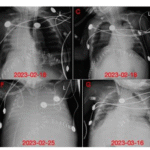

We present a case of a 57-year-old male who experienced ex- tensive bone pain, difficulty in getting up, weakness in walking, and height loss. He had been taking adefovir dipivoxil tablets for the treatment of hepatitis B.